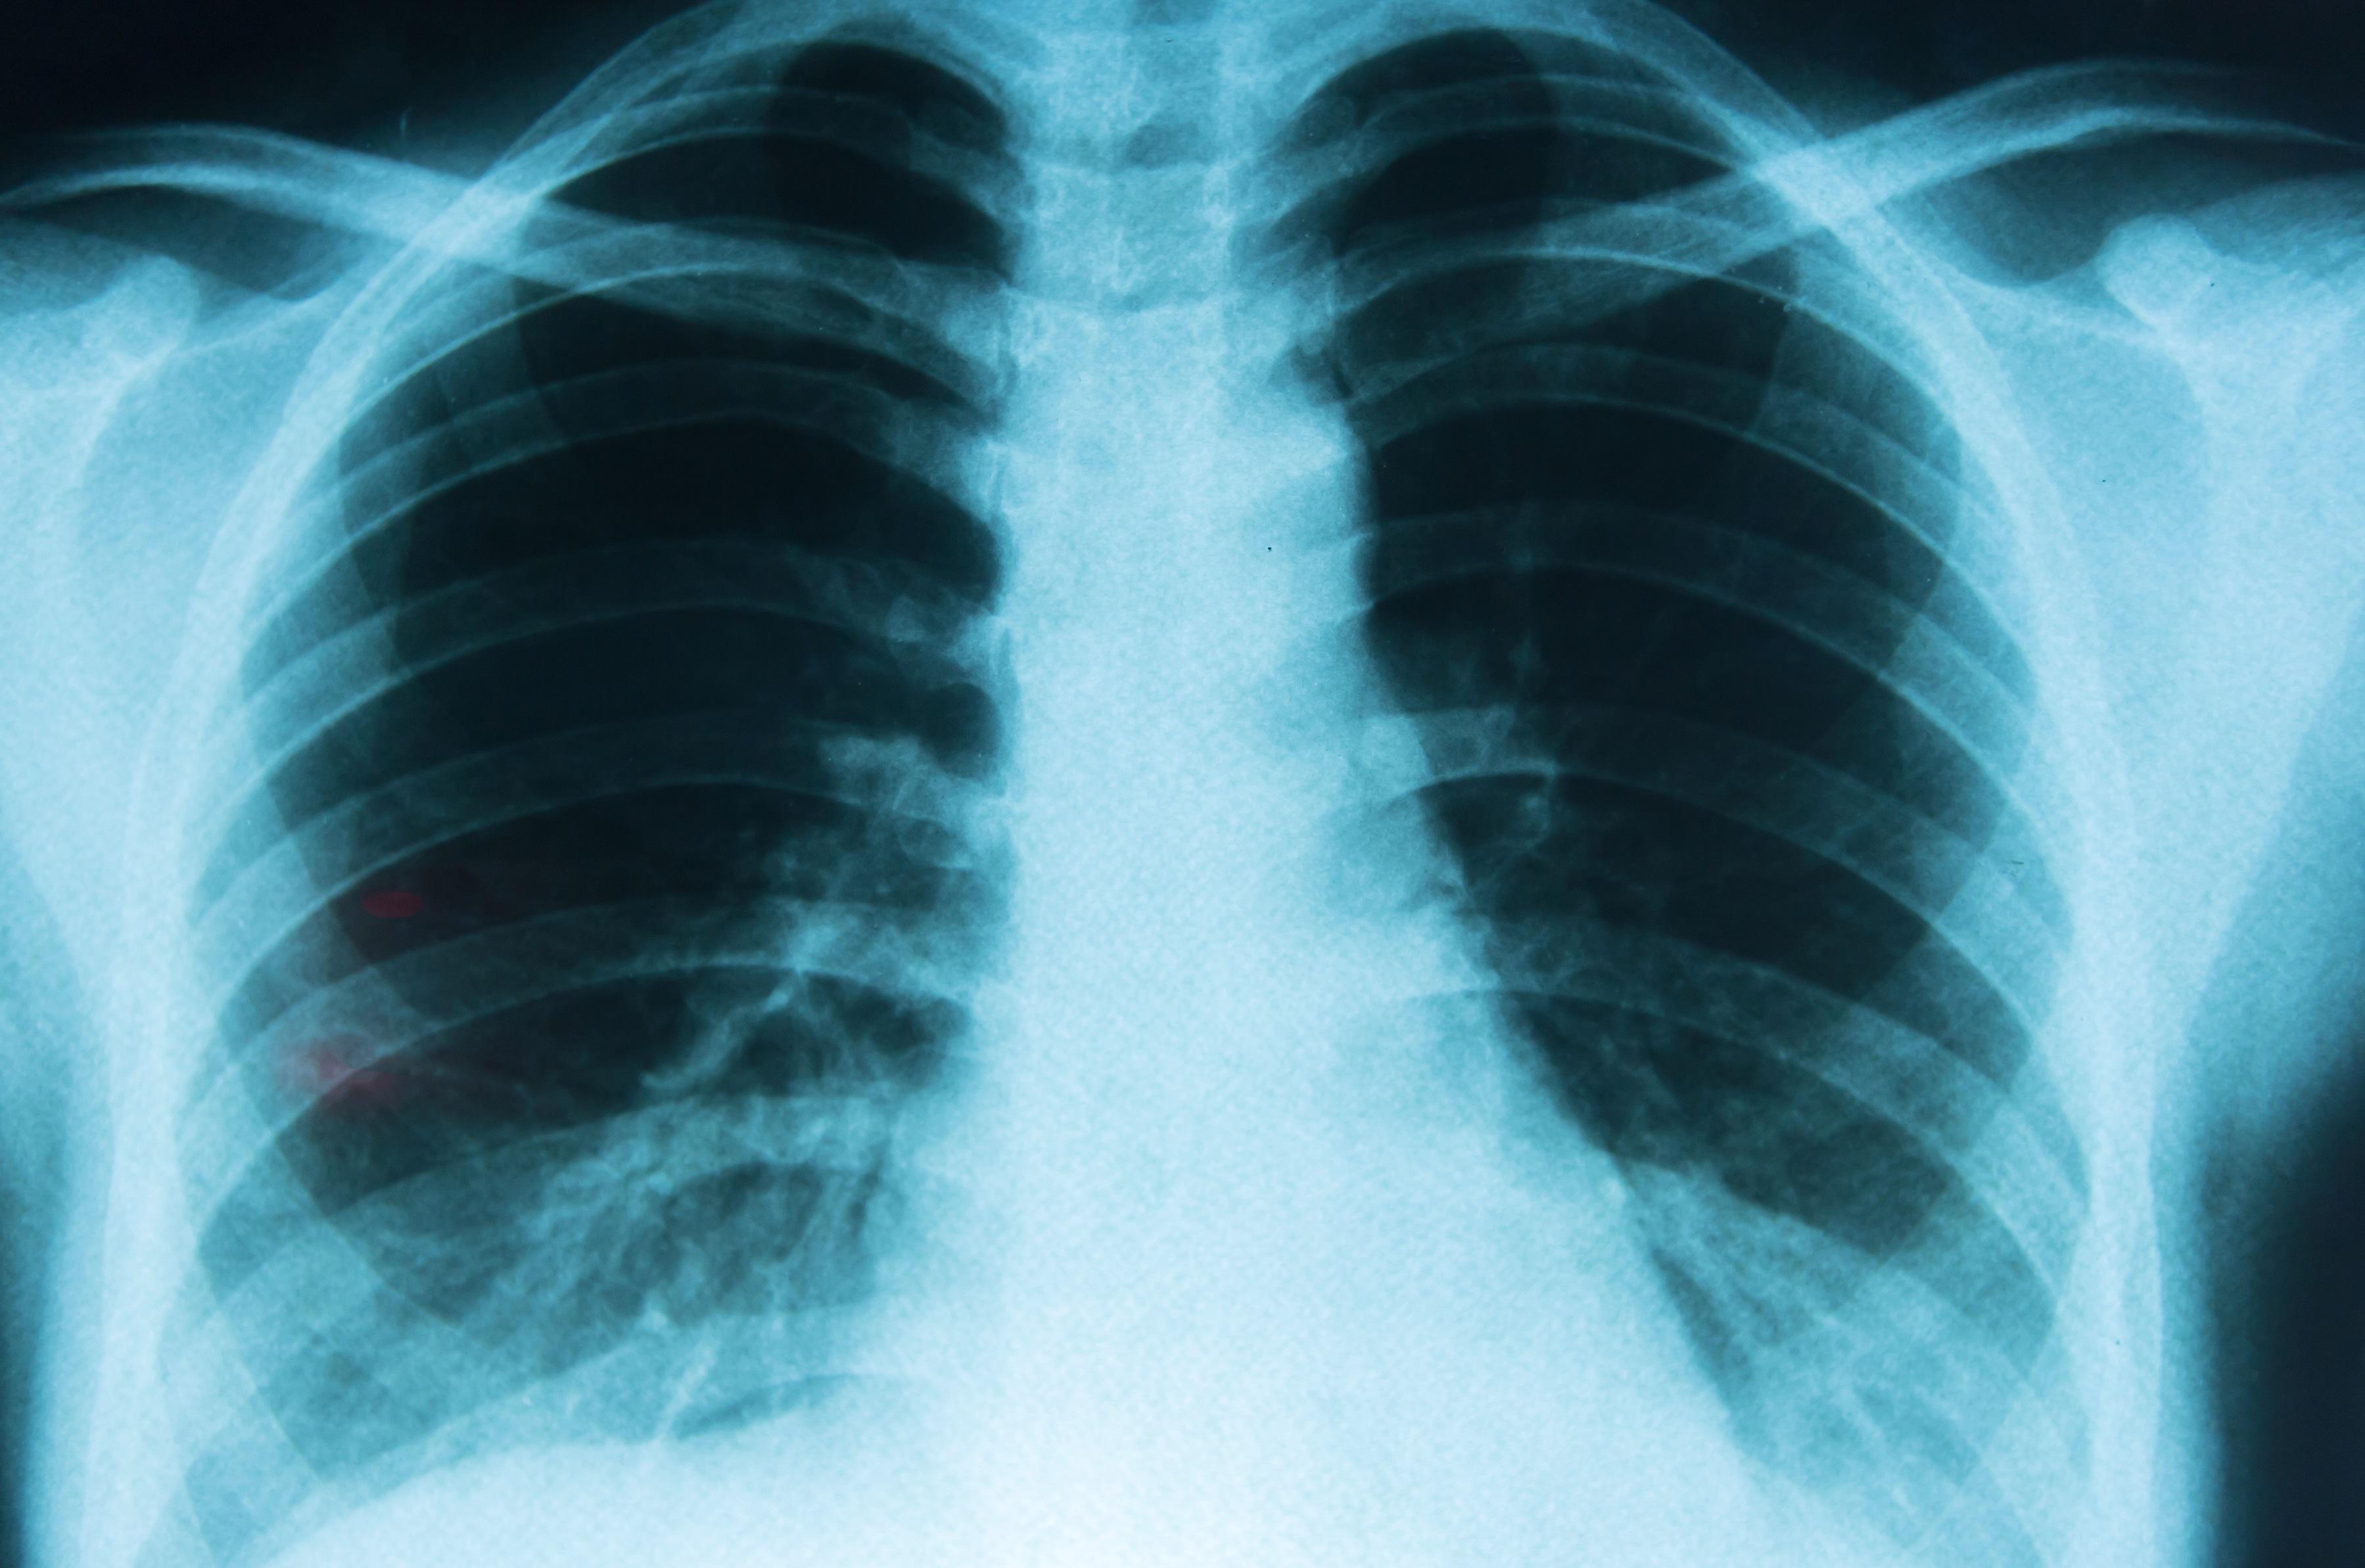

Por lo anterior cada 17 de noviembre se conmemora el Día Internacional de la Lucha Contra el Cáncer de Pulmón, una enfermedad que puede llegar a ser mortal, debido a que poco a poco van minando y dañando los tejidos y el canal respiratorio, sin olvidar que la enfermedad comienza a dar señales de forma tardía, por lo cual el diagnóstico también es realizado cuando ya la enfermedad está en una etapa avanzada.